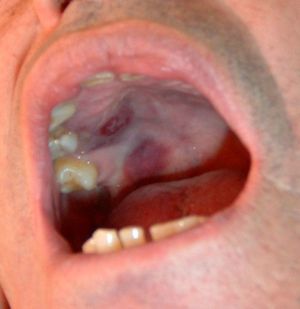

Fifteen months after the diagnosis, there was the appearance of purpuric lesions on the soft palate and on the back of his left foot, which was biopsied. The pathological examination was consistent with KS (Fig. 2) and immunohistochemical study was positive for human herpes virus 8 (HHV-8). Further studies ruled out visceral involvement. A repeat HIV serology was negative. In March 2009, the patient was treated with chemotherapy (doxorubicin), reducing the dose of prednisone and achieving improvement of skin lesions. A CT scan in January 2009 revealed multiple pulmonary nodular lesions that did not appear in previous studies, so an open lung biopsy was performed, finding nonspecific interstitial fibrosis and vascular emphysematous changes in small arterioles. Given the outcome of the lung biopsy and functional impairment of the patient, it was necessary to increase the dose of steroids and we decided to add cyclosporine to the treatment, but these were modified due to the radiographic appearance of pulmonary lesions, although there was clinical and spirometry improvement. Later, in early 2012, the patient had recurrence of KS, with increased skin lesions on the legs, so chemotherapy with betaxolol was administered again. Note that all attempts to reduce steroid treatment below 7.5mg/day have been unsuccessful for worsening respiratory symptoms.